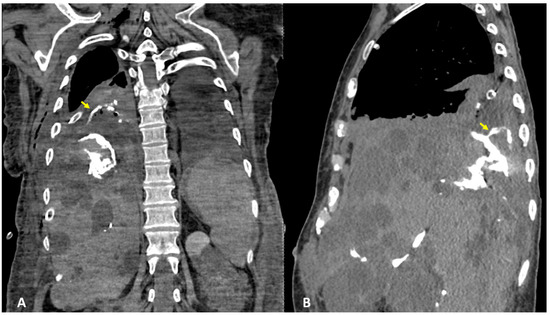

3.4. Case #4: Pancreaticopleural Fistula